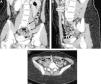

El síndrome de compresión de la vena ilíaca, de May-Thurner o de Cockett es una entidad clínica rara, en la cual la vena ilíaca común izquierda se encuentra comprimida a su paso entre la arteria ilíaca común derecha y la columna. Como consecuencia de la compresión mantenida y del traumatismo causado por la fuerza pulsátil de la arteria sobre la vena, se produce una lesión de la íntima que provoca la formación de membranas o bandas en la luz vascular que dificultan u obstruyen el flujo venoso, lo que favorecería la formación de un trombo. La estrategia terapéutica actual de elección es el tratamiento endovascular con parche venoso y la colocación de endoprótesis, con el objetivo de mejorar el calibre de la luz y permitir un drenaje venoso normal. Presentamos 2 casos clínicos de Síndrome de May-Thurner y revisamos los hallazgos clínicos y radiológicos en la TC computarizada.

Iliac vein compression syndrome (also known as May-Thurner syndrome or Cockett's syndrome) is a rare clinical entity in which the left common iliac vein is compressed when it passes between the right common iliac artery and the spine. The sustained compression and trauma caused by the pulsatile force of the artery on the vein damage the intima and lead to the formation of membranes or bands in the vascular lumen that hinder or obstruct the flow of blood in the vein, favoring thrombus formation. The current treatment strategy of choice is endovascular vein patch angioplasty and stenting with the aim of improving the caliber of the lumen and enabling normal venous drainage. We present two cases of May-Thurner syndrome and review the clinical and CT findings.